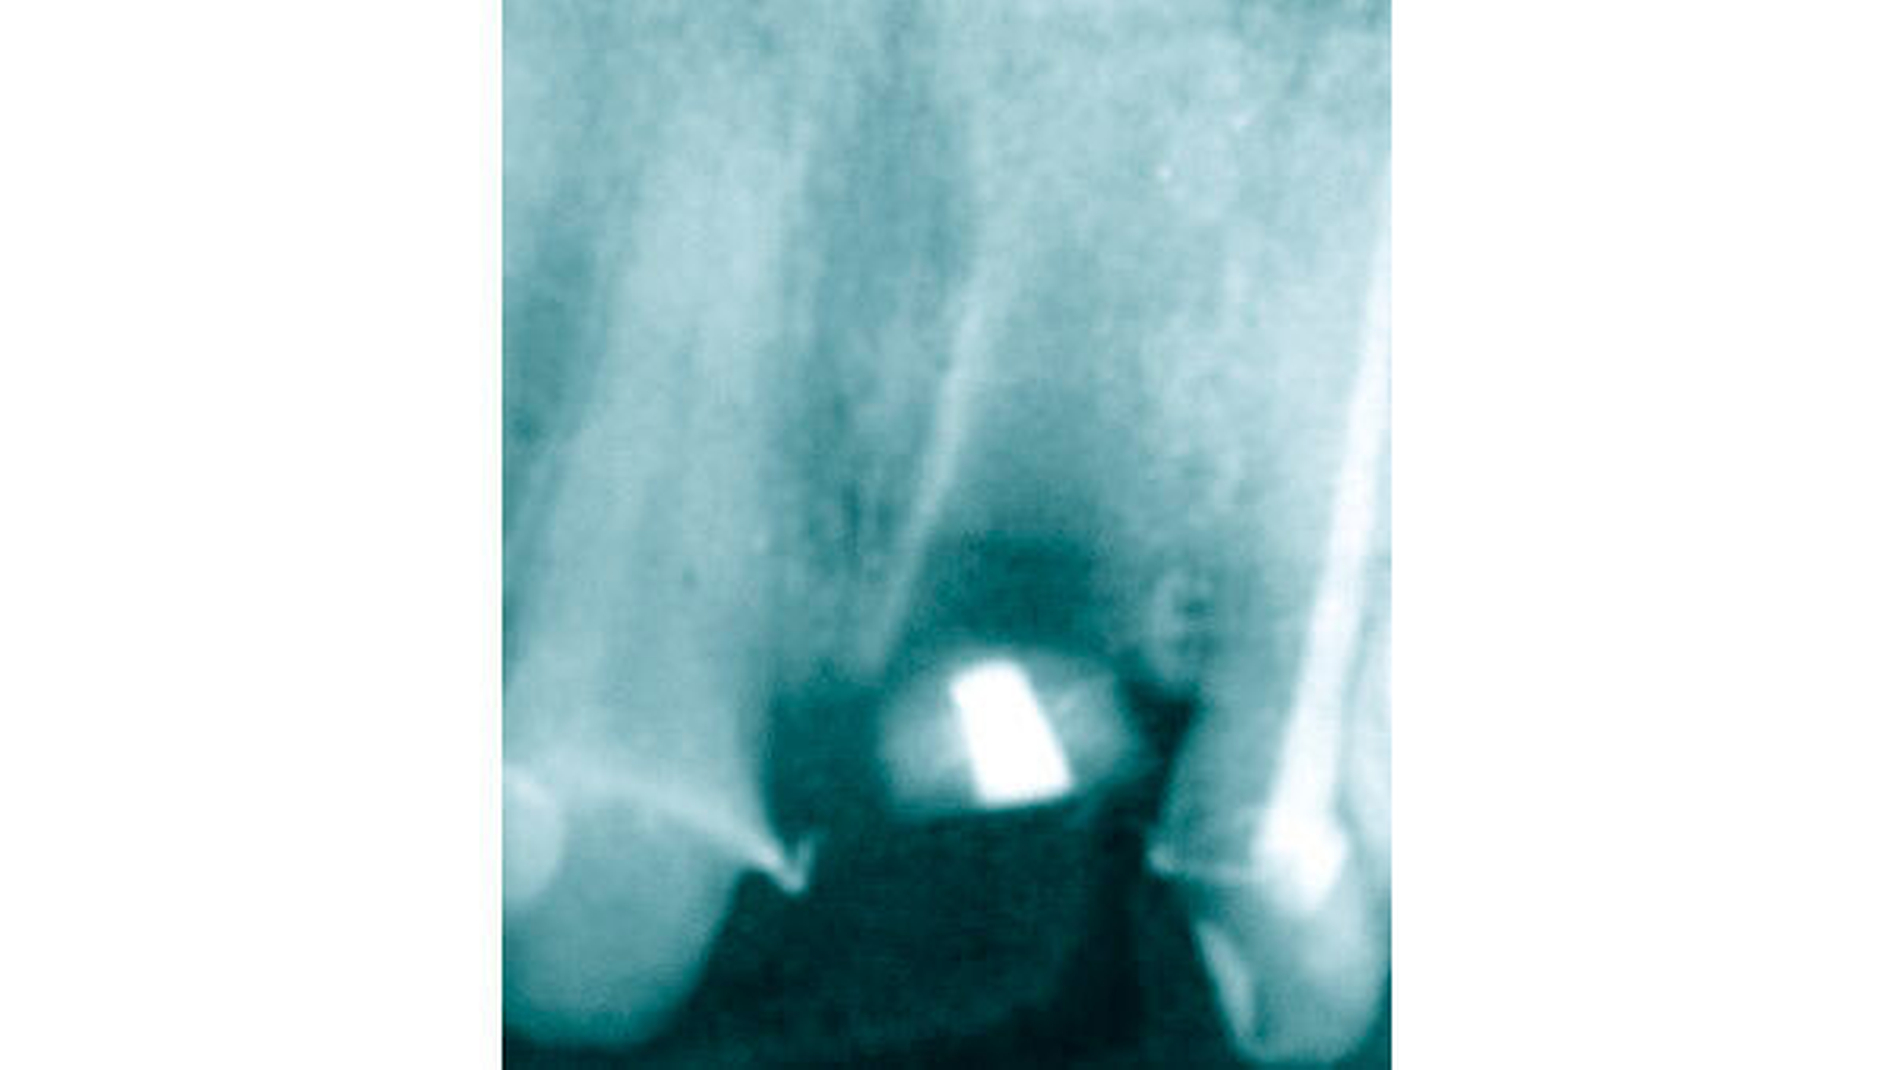

Nach etwa zehn Monaten wurde noch einmal ein Extrusionsimpuls mit zweimaligem Gummiwechsel gesetzt. Etwa zwei Monate später zeigte sich radiologisch ausreichend Knochen bei gleichzeitig taktiler Stabilität (Lockerungsgrad 0), um den Zahn doch erhalten zu können. Die Sondierungstiefen lagen mesial und distal nur noch bei maximal 5 mm, und die ursprünglich durchgängige Furkation lies sich nicht mehr sondieren.

Die Wurzelfüllung wurde suffizient revidiert (Abbildung 11) sowie ein Deep Scaling von 37 bis 35 durchgeführt. Aufgrund der nunmehr guten Prognose wurde im Rahmen einer Gesamtsanierung auch der Zahn 36 mit einer Lithiumdisilikatkrone (Emax, Fa. Ivoclar Vivadent) neu versorgt (Abbildung 12).